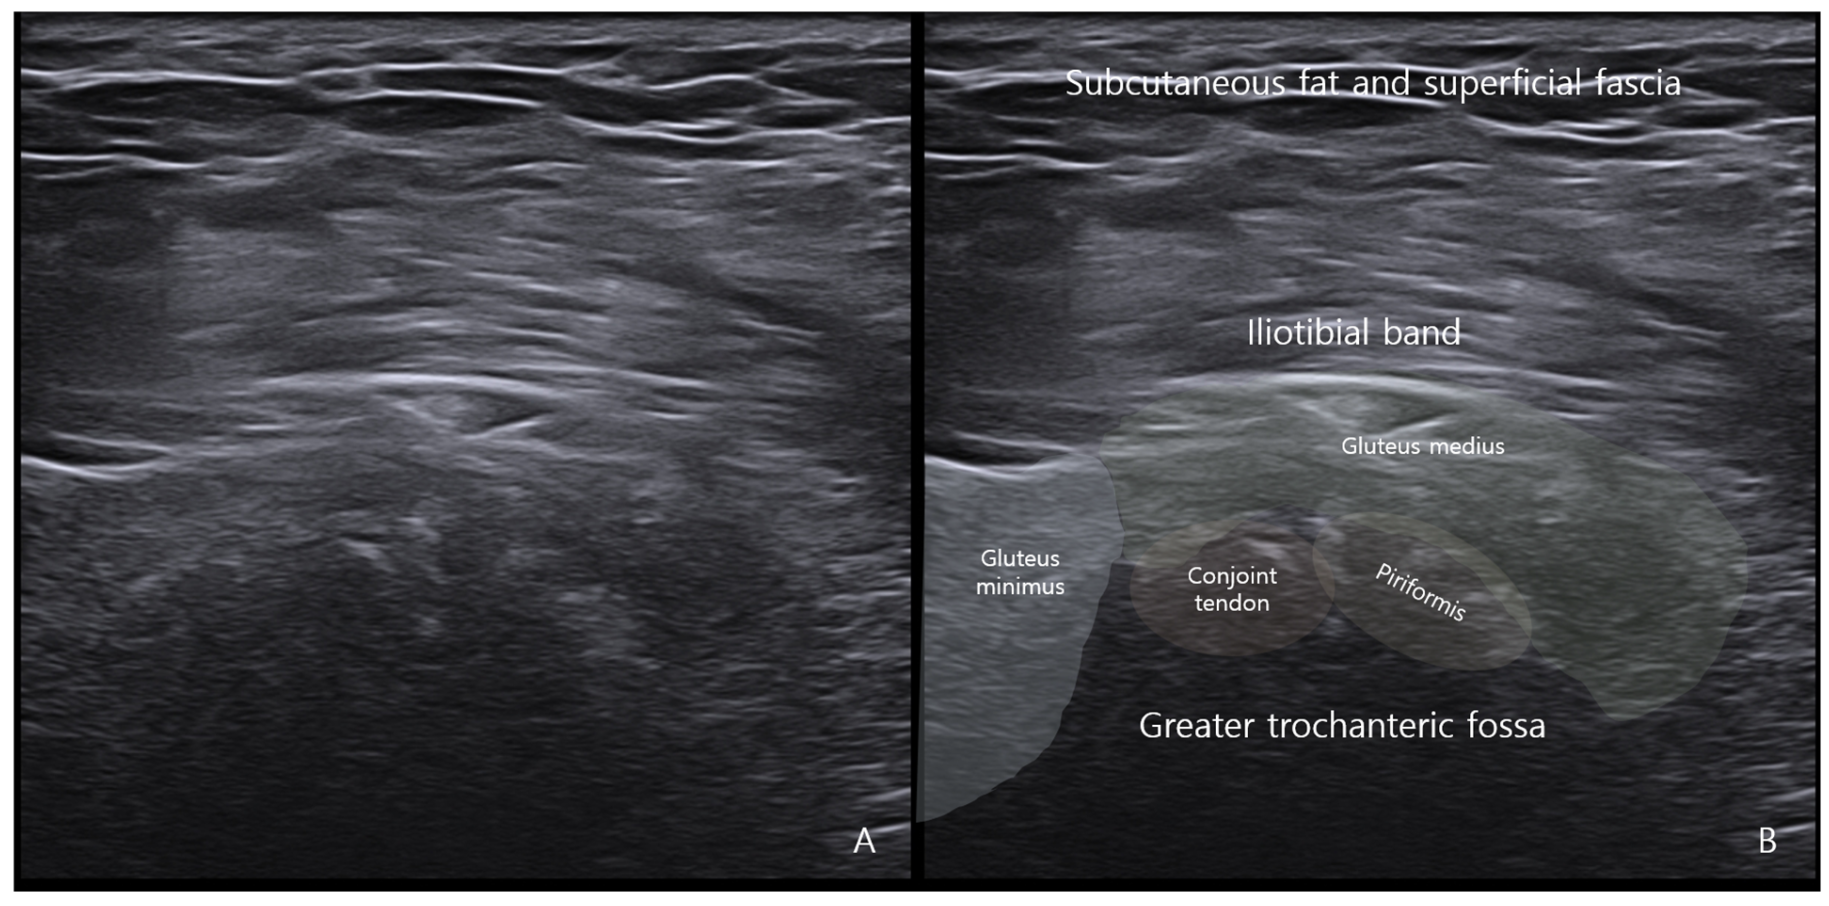

While MRI lacks sensitivity and specificity for detecting peripheral enthesitis, ultrasonography may offer superior sensitivity and greater accessibility in the evaluation of enthesopathic changes [48,49]. Using both grey-scale and power Doppler techniques, ultrasonography allows for concurrent assessment of structural abnormalities (e.g., tendon thickening, hypoechogenicity, enthesophytes, erosions) and active inflammation (increased vascularity) [49]. This capacity makes it particularly effective for detecting enthesopathic changes that may be overlooked on MRI (Figure 7).

Figure 7. A case of deep gluteal syndrome diagnosed by ultrasound. (A) Calcification is observed at the point where the piriformis conjoint tendon attaches to the greater trochanteric fossa. (B) Structures attached to the greater trochanter were schematically and named using ultrasound.